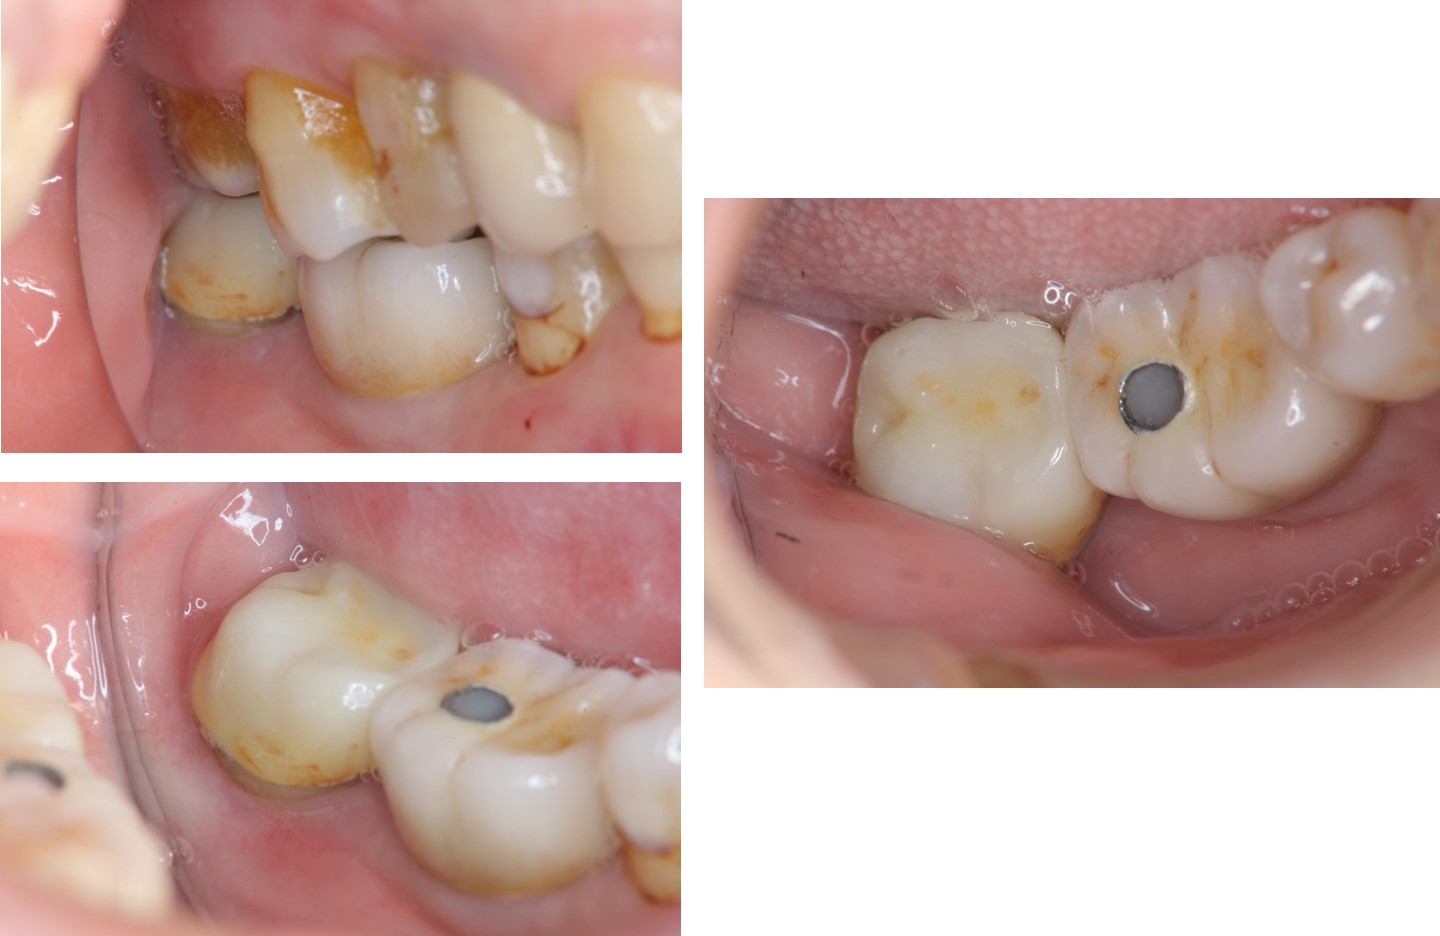

膺復前評估牙齦、牙齒狀態